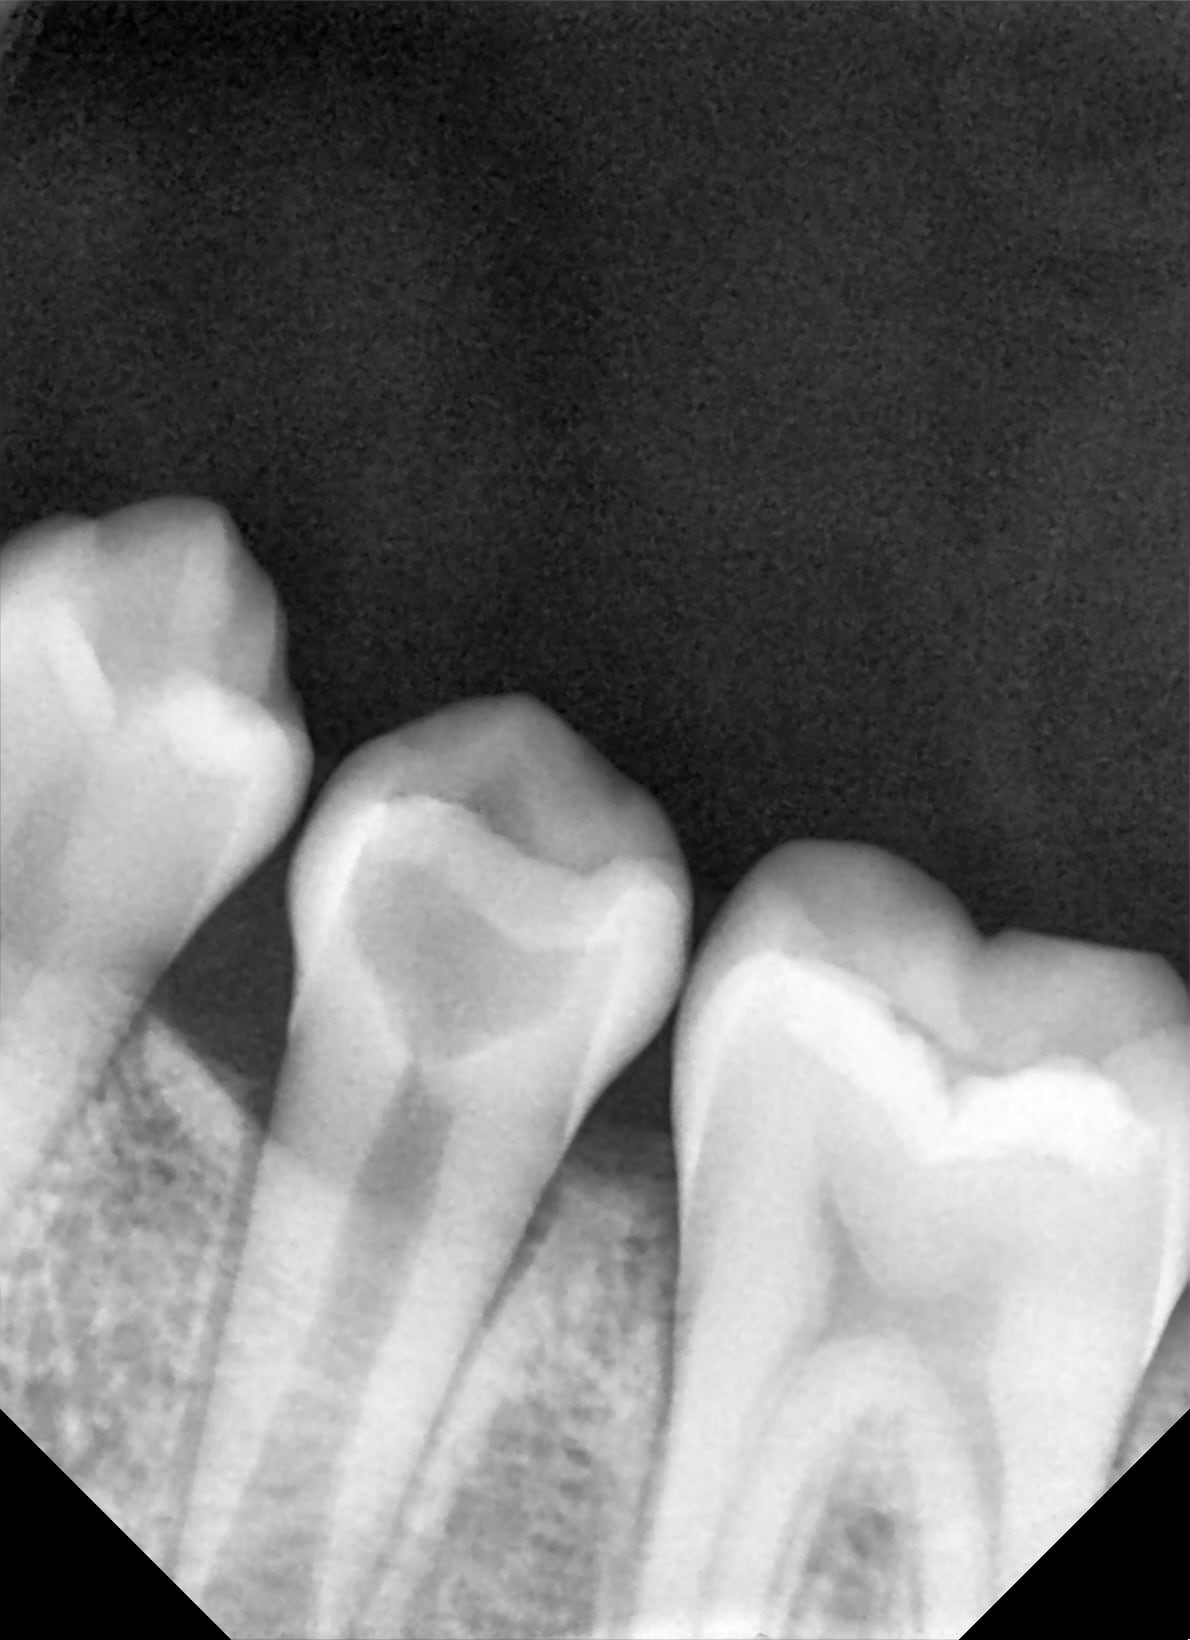

combien de temps entre les 2 radios

trois ans que ça couve.

mais jolie. j'ai le cone radio très angulé pour avoir l'apex (presque à 45°) c'est ptet ça.

truc bizarre c'était pas une carie sur cette 5 du moins pas au début. de la dentine toute étrange, sans émail dessus qui à mal fini.

Chouette apexification , il ne reste plus qu’a la flinguer propre ;0))